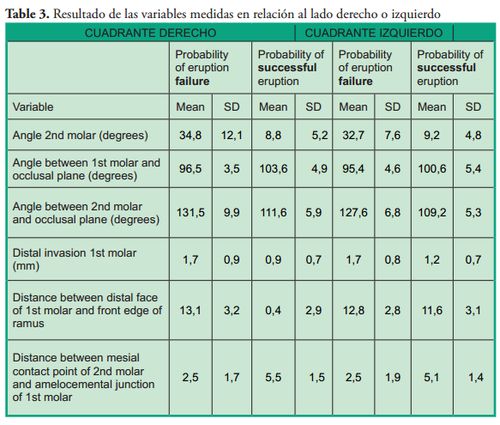

Patients with probability of eruption failure amounted to 1.43% of the sample, their mean age was 10 ± 1.7 years, and 73.3% of them were female. The variable used to determine the probability of success or failure of eruption was the angle of the second molar: an angle equal to or smaller than 24° showed probability of successful eruption, whereas an angle equal to or greater than 25° was considered with probability of eruption failure according to the average established by Evans in 1988 (average of 25° with a range from 15° to 65°). Tables 1, 2 and 3 show the results of the variables studied and their relation with the probability of teeth eruption or noneruption, unilateral or bilateral presence and distribution per quadrant.

This study of mixed dentition was conducted in the field of dental development with the aim to help prevent dento-maxillary anomalies in permanent dentition. We evaluated variables already studied by other authors to determine if this sample behaves in a similar way as previous samples or if it differs in some aspects. We found a 1.43% frequency of eruption failure of the second permanent molar. This percentage is similar to the results of Bondemark & Tsiopa in 2007 (1), who observed a prevalence of 0.8%, and of Cho et al. in 2008, which was of 1% (2). It differs from the findings of Sonis & Ackerman in 2011: 8.5% (8). Regarding the age of patients, we found a mean age of 10, as opposed to Sonis & Ackerman who reported a mean age of 11.2 years (8); 12.8 years for Evans (6) and 15 years for Magnusson & Kjellberg in 2009 (11). Regarding the angle of the second permanent molar, this study found a range from 25 to 80 degrees, which is similar to the findings of Cho et al. (13 to 75 degrees); Evans (15 to 65 degrees) and Sonis & Ackerman (19 to 33 degrees). The ranges described in the measurements of this angle are quite similar, which allows us to infer that patients with an angle included in the above ranges should be periodically checked. The invasion of the distal space of the first molar by the permanent second molar was of 1.7 mm in this study, which is greater than the invasion described by Sonis & Ackerman (0.57 mm). The angle of the second molar with regard to the line of the occlusal plane of this study was of 129.5 ± 8.5, which is smaller than the angle found by Shapira et al. in 2011 (134.66 ± 12.07).

The prevalence of risk of impaction of the lower second molar is low. The invasion of the distal face of the first molar in this study was greater than what was found in other studies. Risk of unilateral impaction is more frequent. Greater frequency of risk of impaction was found on the left side. No correlation was found between the size of the distal space of the first molar and the front edge of the ramus, and the risk of impaction of the second molar.